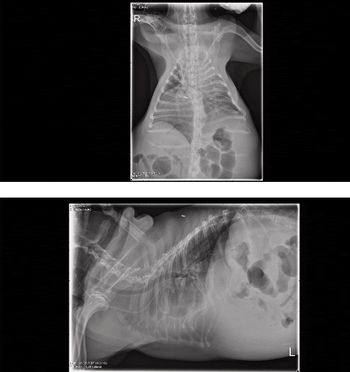

The principles of management of patients with severe lung disease and injury are summarized and the cases depicting the use if these management techniques are presented.